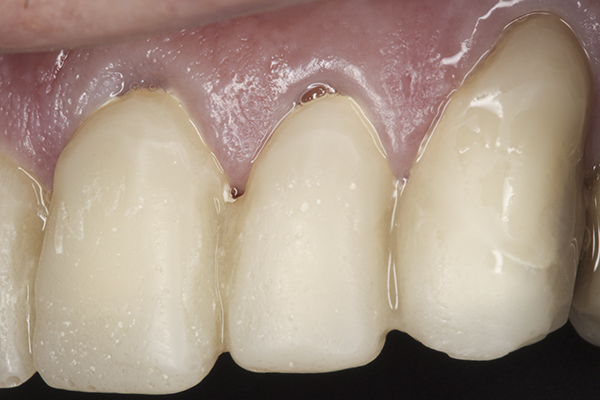

(38.) Postoperative right anterior, close-up view.

Figure 38

(39.) Postoperative anterior, close-up view.

Figure 39